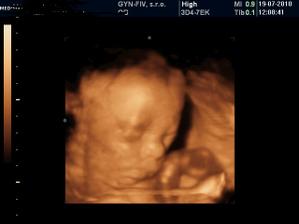

@grenka ale pekne bruchane...pri chalanovi zvykne byt zena pekna a priberie viacmenej len do bruska...ze nie je to rozliate vsade..tak aspon nejake pozitivum...tie uzv na stanovenie hmotnosti su len orientacne...v 31tyzdni mi povedali ze 2080 a v 32tyzdni ze 1800...chapes...?akoze to za tyzden...co mal este pribrat tak schudol...xixi...a odvtedy mi nikto nerobil uzv...ale objednala som sa sukromne bud tyzden...tak uvidime kolko bude mat